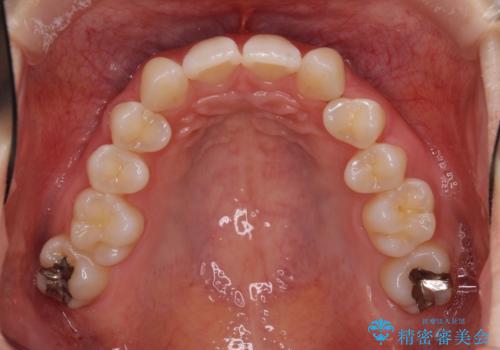

上顎前歯が2本欠損 インビザラインによる叢生の解消

- 深い咬み合わせと前歯のデコボコを気にして来院された患者様です。

上顎前歯2本が欠損しているため、妥協的なゴールを設定しインビザラインで矯正治療を行うこととしました。

上下前歯の大きさのアンバランスにより、深い咬み合わせと奥歯の咬みにくさがなかなか解決されず、治療に長期間を要することとなりました。